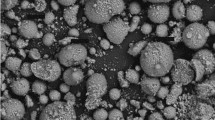

SEM micrographs (Fig. 1) indicated that the Ti particles added to the culture medium were irregular in shape and less than 1.0 μm in size. The laser particle size analyser confirmed that these particles had a mean size of 0.24 μm with standard deviation of 0.10 μm, whilst the minimum and maximum sizes were 0.04 μm and 1.64 μm, respectively (95% of particles <1.00 μm; 90% particles <0.50 μm) (Fig. 2). Therefore, the Ti particles used were judged to be in the submicron size range.